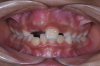

The following case illustrates the complete surgical/orthodontic treatment sequence for an impacted maxillary right central incisor. An 8½-year-old patient presented with a chief complaint of crowded teeth. The maxillary left central incisor was the only erupted incisor at the time of consultation (Figure 2 and Figure 3). Crowding was clinically diagnosed visually by the prominence of the unerupted right central incisor in the vestibule, and this was confirmed with a panoramic radiograph (Figure 4).

Fig 4. Initial panoramic x-ray.

Figure 4